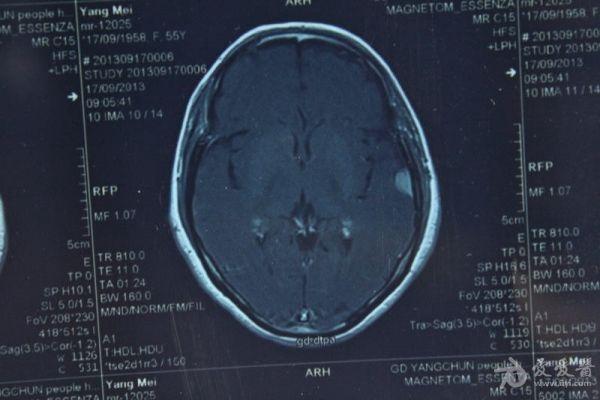

脑部占位病变CT,MRI图片,请帮忙诊断

最近感图样,无其它脑病病史

考虑脑膜瘤!!

磁共振没有平扫,增强矢状位没找到病灶。像脑膜瘤。

图片不是很清楚,应该是脑膜瘤!